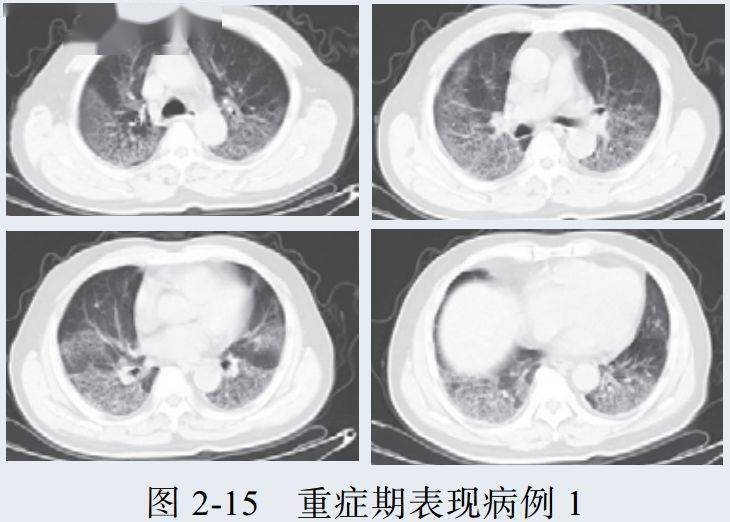

三、重症期征象

新冠肺炎肺部病变一般在发病后 14 天左右达到高峰,少部分病例急剧进展,病变累及双侧全肺,呈白肺征象,其内可见空气支气管征,双侧胸腔可有少量胸腔积液,临床纳入危重症管理

根据既往病理学机制提示肺泡腔有大量纤维素性渗出

病例展示

3. 重症期表现为大范围肺组织密度增高实变,少数呈白肺征象